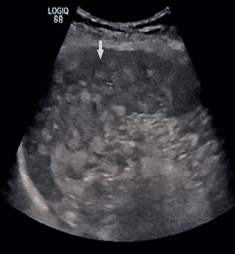

Identify this image.

Splenic granulomas